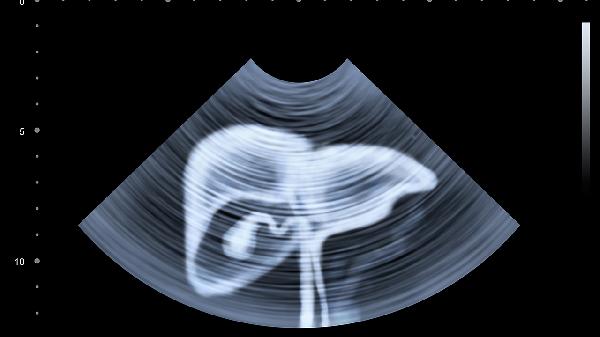

日常应注意腹部保暖,避免暴饮暴食和过度劳累,养成细嚼慢咽的饮食习惯。若疼痛伴随发热、呕吐、便血等警示症状,或疼痛规律改变、夜间痛醒,应立即前往医院消化内科就诊,通过胃镜、腹部超声等检查明确病因。长期反复发作的隐痛可能提示慢性疾病进展,定期体检和规范治疗有助于防止病情恶化。